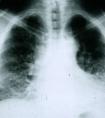

肺损伤或孤立性肺结节是一种肺部病变,一些患者在因某些原因进行X-射线检测时,可能会被偶然检测到肺部损伤。虽然医生通常在发现病变时会担心癌症存在的可能,但事实上在大多数情况下这些肺...